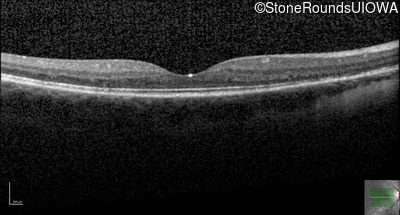

Optical Coherence Tomography - Left - 20/50

Exemplar / OCT Stack